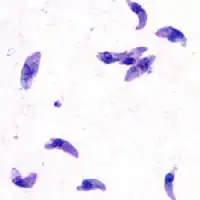

| Toxoplasma gondii tachyzoites | |

The Eucoccidiorida are an order of microscopic, spore-forming, single-celled parasites belonging to the apicomplexan class Conoidasida. Protozoans of this order include parasites of humans, and both domesticated and wild animals including birds. Among these parasites are the Toxoplasma gondii that cause toxoplasmosis and Isospora belli, which results in isosporiasis.